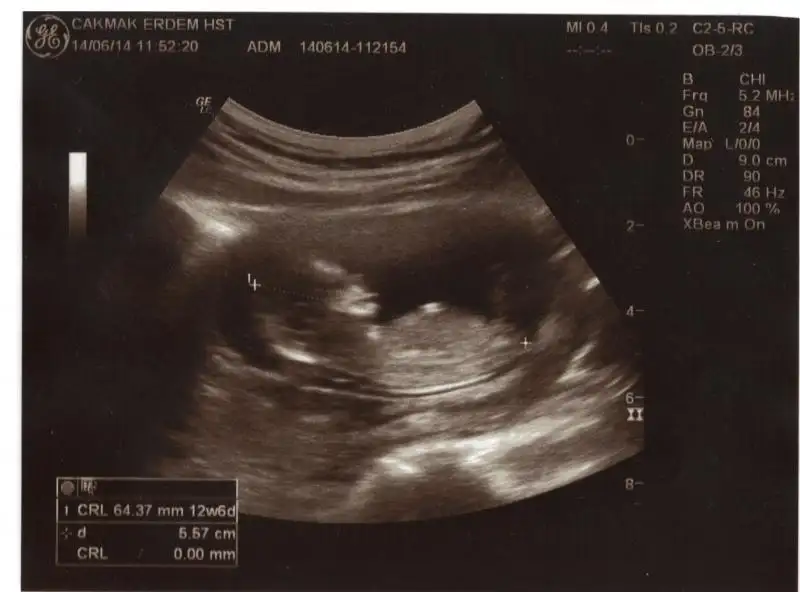

dr soylemeden siz gorun genital nub teorisi ( bebegin cinsiyeti)

İlk sayfadakı resımlere bakaraktan kendî usgmede baktım 11 haftalık nub dedıgınız cıkıntı yukarı doru erkk dedi m